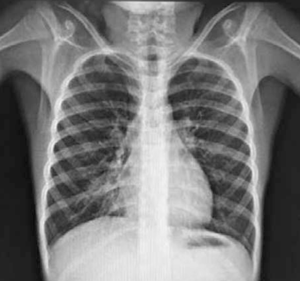

Adolescente de 13 años, sexo femenino, procedente de Montevideo, buen crecimiento y desarrollo, carné esquema de vacunación vigente, medio social, económico y cultural aceptable. Antecedentes familiares de padre y hermana con asma, abuela paterna con asma y aspergilosis broncopulmonar alérgica a los 50 años. La primera evaluación por neumología fue a los 9 años, se presenta con tos crónica catarral desde los 6 meses de vida, sin predominio estacional, no expectoración, drenaje postural, broncorrea, ni sinusitis. Se acompañaba de otitis crónica serosa que requirió colocación de tubos transtimpánicos a los 4 años, con persistencia de secreciones de oído medio, hipoacusia e impedanciometrías alteradas. Al examen se destaca: índice de masa corporal (IMC): 16,7 kg/m² (percentil 15); pleuropulmonar: frecuencia respiratoria 16, saturación de oxígeno ventilando espontáneamente al aire 98%, pico flujo espirado 350 L/m, moviliza secreciones con la tos, no remodelación de tórax, ni hipocratismo digital. No presentaba pólipos en la rinoscopía. Cardiovascular normal. En la radiografía de tórax se observa opacidad inhomogénea en lóbulo medio (Figura 1). La radiografía de senos faciales muestra opacidad de ambos senos maxilares (Figura 2). Con sospecha de bronquiectasias se solicitan estudios para descartar FQ, inmunodeficiencias, malformación congénita de la vía aérea y discinesia ciliar. Los resultados de tres test del sudor fueron normales: Cl 23 meEq/l (159 mg sudor), Cl 14 mEq/l (215 mg), Cl 19 mEq/l (180 mg), y la evaluación inmunológica fue normal. El exudado faríngeo no desarrolló gérmenes. La tomografía de tórax de alta resolución muestra múltiples bronquiectasias en lóbulo medio, disminuido de tamaño por atelectasia (Figura 3). Se realiza fibrobroncoscopía con lavado bronquioalveolar, en vistas de valorar la vía aérea, y valoración infecciosa. Se descarta lesión anatómica o dinámica en la vía aérea y cuerpo extraño, y el estudio bacteriológico y micológico fueron negativos. Con sospecha de DCP, se realiza biopsia de la mucosa bronquial y microscopía electrónica. Las muestras obtenidas fueron fijadas en glutaraldehído al 2,5% en tampón fosfato 0,1 M (pH: 7,2 - 7,4), y trasladadas a 4 grados al laboratorio de biología celular, Instituto de Investigaciones Biológicas Clemente Estable. Se observaron alteraciones ultraestructurales consistentes con DCP. Se realiza cepillado nasal de ambas fosas nasales, observadas vivas e incubadas a 37° al microscopio de contraste de fase en medio de cultivo médium 199 para determinar morfología, frecuencia y patrón de batido ciliar, constatándose movilidad ausente en todos los campos. La microscopía electrónica muestra ultraestructura ciliar con patrón 9+2, con ausencia de ambos brazos de dineína. El diagnóstico de funcionalidad con inmovilidad ciliar absoluta, cilios de ultraestructura con defecto de brazos internos y externos de dineína, confirma la DCP. Se solicita estudio genético molecular con secuenciación del gen DNAH5, que muestra una variante probablemente patológica con presencia en homocigosis de una duplicación c.10196dupT mutación frameshift p. Cys3400Metfsx54, no se encuentra en base de datos ni en la bibliografía consultada, y otra de significado incierto con presencia en heterocigosis de la variante c.A8387G: p.D2796G en el gen DNAH5. En la evolución, la paciente persiste con igual sintomatología, los cultivos de expectoración iniciales fueron negativos. A los 13 años el estudio bacteriológico de expectoración desarrolla Pseudomonas aeruginosa, se realiza tratamiento con gentamicina nebulizada y ciprofloxacina vía oral por 21 días. Los cultivos de control muestran desarrollo de Pseudomonas aeruginosa, por lo que se indica tobramicina inhalada por 28 días. Persiste desarrollo de abundantes colonias y se inicia colistina nebulizada cada 12 horas, inicialmente por tres meses, luego mensual alternando con tobramicina inhalada. De la evolución funcional, presentó espirometrías normales, con valores de volumen espiratorio forzado en el primer segundo (VEF1) estables de 95% del predicho, distancia recorrida en 6 minutos sin desaturación en la mar cha, ecocardiograma Doppler normal y audio metrías normales. En la tomografía de tórax, a los 13 años, persisten bronquiectasias asociadas a atelectasia en lóbulo medio, sin cambios significativos con respecto a la tomografía previa, hiperinsuflación compensadora del resto de los lóbulos; aisladas bronquiectasias en segmento basal medial de lóbulo inferior derecho, aso ciado a imágenes de árbol en brote. Agrega bronco rrea mucopurulenta 10 cc al día. Presentó adecuada adhe rencia al tratamiento con fisioterapia dos veces por día en domicilio, asistida por fisioterapeuta tres veces a la semana. El tratamiento antibiótico continuó con colistina nebulizada y cipro floxacina vía oral. Realiza ejer cicio y danza de forma regular.